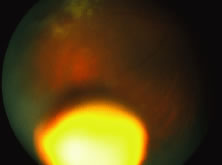

A disseminated form of congenital HSV occurs with involvement of the brain and viscera, principally the liver, adrenal glands, kidneys, lungs, and gastrointestinal tract. The child typically presents with fever, poor feeding, hypoactivity, and respiratory difficulty (Fig. 30). This is the most severe form of congenital herpetic disease with the poorest prognosis. More localized forms of congenital HSV infection may include the CNS, eyes, skin, or oral cavity. Overall, 20% of neonates contracting herpetic infections have ocular involvement.125

Fig. 30. Herpes simplex retinitis in a newborn manifested by fulminant panretinal involvement of white areas of retinitis and variable hemorrhage. The child also suffered from herpetic encephalitis and skin disease.